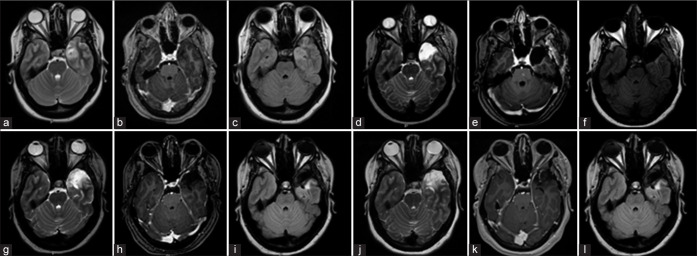

Case description: A 20-year-old female, not known to have any medical illness, presented to the emergency department with speech arrest that progressed to generalized tonic-clonic seizures. Brain magnetic resonance imaging showed a T2 hyperintense nonenhancing cortical-based heterogeneous mass in the left medial temporal lobe and adjacent inferior temporal gyrus measuring 2.7 × 2 × 2.5 cm with no susceptibility signal or diffusion restriction. Electroencephalogram (EEG) showed left temporal epileptiform discharges. She underwent left frontotemporal craniotomy and tumor resection. The light microscopic examination of the tumor revealed a low-grade infiltrative neoplasm. There was a classical appearance of round cells with perinuclear halo, immunopositive for olig-2, glial fibrillary acidic protein (GFAP), and cluster of differentiation-34. There was B-Raf protooncogene, serine/threonine kinase (BRAF) c.1799T>A (p.V600E) point mutation and absence of isocitrate dehydrogenase (IDH) 1 and 2 hotspot mutations. The overall findings were diagnostic of PLNTY.